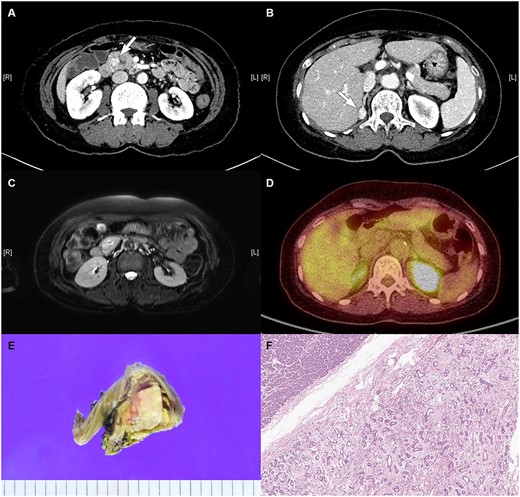

A 57-year-old female was referred to the outpatient department of our institute since an enhanced abdominopelvic CT conducted in another hospital showed (i) a 3.3-cm-sized hypervascular mass with internal cystic changes in the uncinate process of the pancreas and (ii) a 1.6-cm-sized enhancing fat-containing lesion in the right adrenal gland (Fig. 1a and b). At the initial outpatient consultation, the patient denied any specific symptoms. She had no noteworthy medical history except hypertension and dyslipidemia requiring medication. Her family history was notable for pancreatic cancer in her father and sister, gastric cancer in her brother, and type 2 diabetes mellitus in her mother.

Radiologic images of the (A) pancreatic mass in the uncinate process of the pancreas on CT, (B) right adrenal mass on CT, (C) pancreatic mass on MRI, and (D) pancreatic mass on PET. (E) Gross pathology: well-demarcated whitish to tan-colored mass with mild hemorrhage and (F) microscopic findings: variably cystic small to medium-sized ductular structures surrounded by collagenized stroma.

Magnetic resonance imaging (MRI) confirmed a 3.3-cm-sized hypervascular mass in the pancreas uncinate process and a 1.6-cm-sized enhancing fat-containing lesion in the right adrenal gland, corroborating the CT findings (Fig. 1c). PET-CT revealed increased fluorodeoxyglucose uptake with equivocal significance for malignancy between the pancreas head and duodenum and focal increased uptake in the right adrenal gland (Fig. 1d).

During the operation, the pancreas was soft, and the surgical specimen revealed a well-defined whitish to tan-colored mass (3.2 cm) with slight hemorrhage (Fig. 1e). The pathological examination showed pancreatic hamartoma. Microscopic findings showed a well-demarcated mass with an adenosis-like structure composed of small to medium-sized ducts with stromal fibrosis (Fig. 1f). Immunohistochemical staining demonstrated positive staining for CK7 and CK19 and focal positivity of the S-100 protein in ductular structures and positive staining for Bcl-2 in spindle cells.